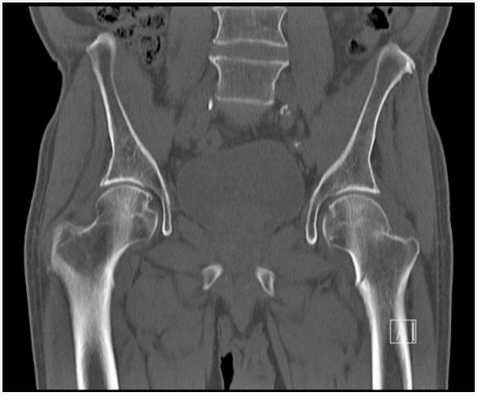

3D-реконструкция КТ тазобедренных суставов, прямая проекция

Тазобедренный сустав - один из самых крупных у человека, на него приходится большая нагрузка, что повышает вероятность травматизации. В норме суставная головка соответствует впадине, костная и хрящевая ткань без деструктивных изменений, движения в полном объеме, а болевые ощущения отсутствуют.